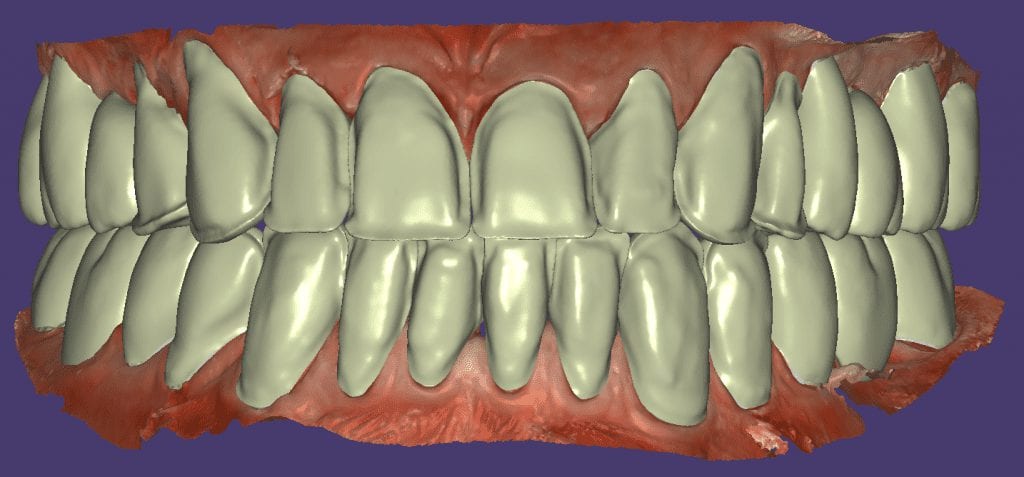

Once the appropriate library is chosen, the digital wax ups are performed. In the subsequent photos you can see the transparent overlay of the wax-ups to the original position of the existing dentition

Once the case is designed to the ideal vertical dimension then multiple shells can be fabricated for treatment. The wax up model can be uniformly reduced by .5mmm’s circumferentially and a temporary shell can be designed. Once the teeth are prepared, these shells can be relined and seated onto the preps.